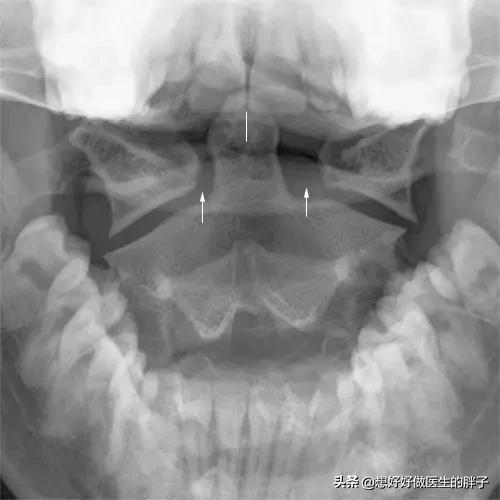

En ce qui concerne la description du sujet, il y a des antécédents de migraines depuis plus de vingt ans, et la douleur a commencé à se manifester près des points Fengchi, ce qui, si le problème est dû à la musculature sous-occipitale, suggère que le problème musculaire peut devenir plus important. Il est recommandé de procéder à un examen initial d'unRadiographie de la colonne cervicaleIl est également conseillé de vérifier la présence d'anomalies de la courbure cervicale.Film bouche ouverte du rachis cervicalAfin de déterminer s'il existe une anomalie anatomique au niveau du rachis cervical, c'est-à-dire du rachis atlanto-axial, il est possible d'établir un diagnostic préliminaire de l'état du patient et d'observer s'il y a ou non des problèmes au niveau du rachis cervical.